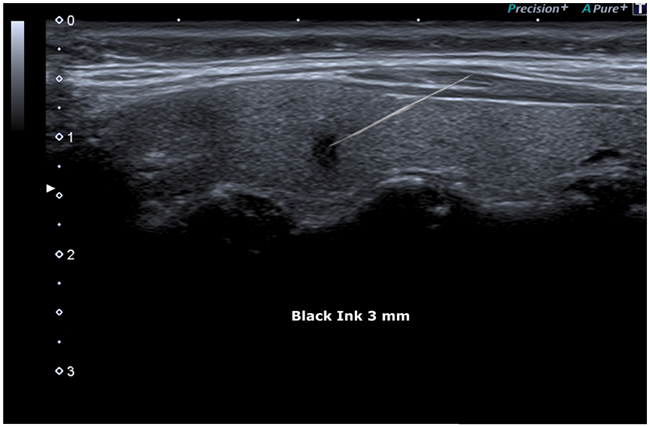

FNAC procedure was proposed to the patient and, after informed consent had been obtained, it was performed under ultrasound guidance (Figure 8).

Figure 8: FNAC (Fine Needle Aspiration Cytology) Showed under guide.

Despite the small size of the lesion, the diagnostic image was strongly suspicious for malignancy and the FNAC procedure determined accurate detection of malignancy. Based on nuclear crowding and presence of prominent nucleargroves and pseudoinclusions FNAC was classified TIR5 according to the Italian consensus [20] and Category VI according to the Bethesda Classification [21].